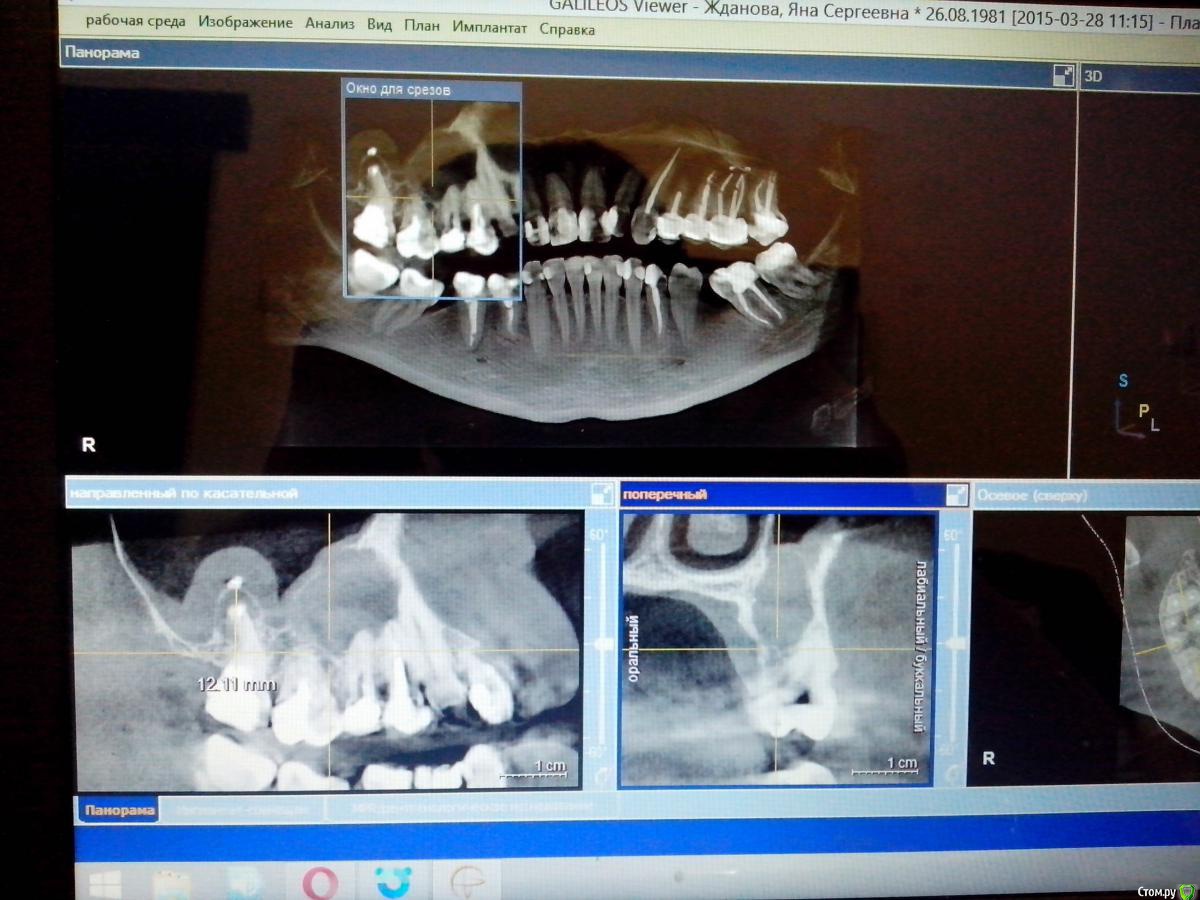

yasya Опубликовано 6 марта, 2016 Поделиться Опубликовано 6 марта, 2016 Здравствуйте! Прошу совета. Обнаружили кисту,в которую входит уже три зуба(4,5,6) и 7-ка со своей кистой. До обнаружения ничего не беспокоило, никак себя не проявляла. Уже смирилась с тем, что три зуба идут под удаление. Но седьмой хирурги удаляют, а пара терапевтов берутся перелечить. Стоит еще за него побороться? Ссылка на комментарий

St. Опубликовано 7 марта, 2016 Поделиться Опубликовано 7 марта, 2016 Покажите ещё другие срезы КТ или всё полностью выкладывайте. По этому одному снимку сказать нельзя. Ссылка на комментарий

Гарриевич Опубликовано 8 марта, 2016 Поделиться Опубликовано 8 марта, 2016 Выложите КТ полностью, покручу Ссылка на комментарий